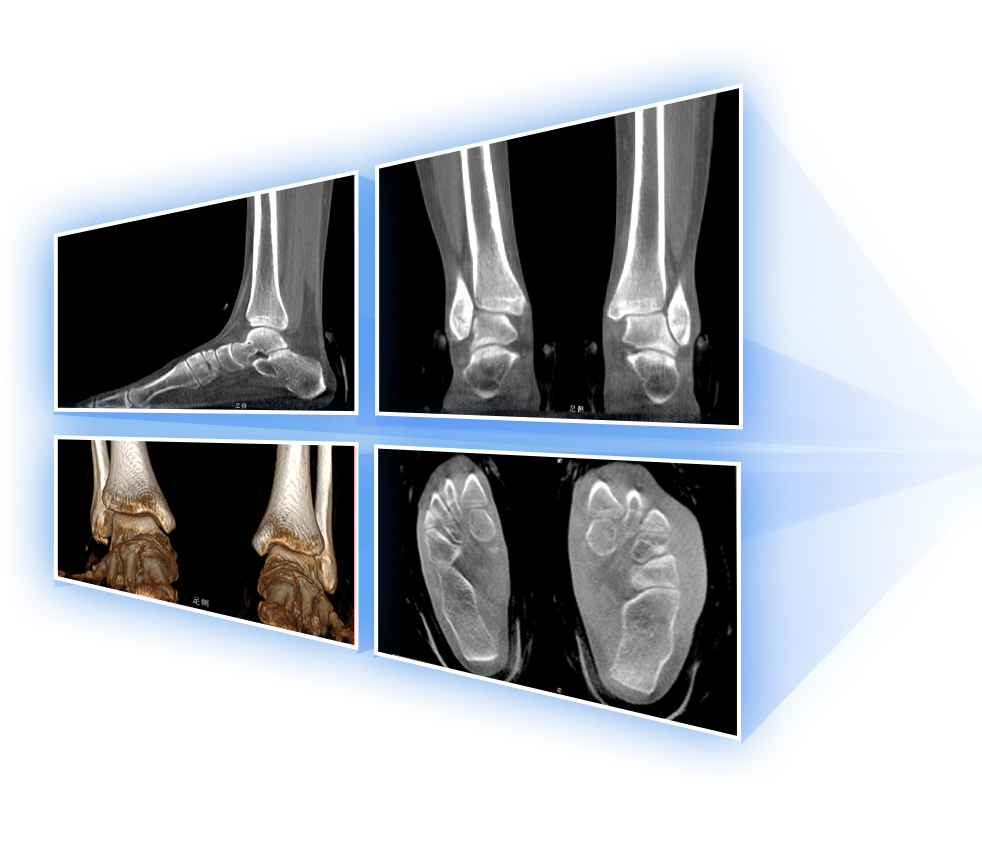

• 足踝

2D+3D一站式快速检查

支持双腿或双侧髋关节扫描 | 方便对比,降低漏诊误诊

FOV 350mm